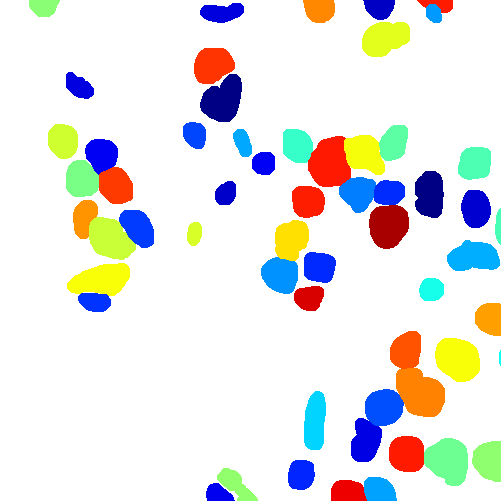

The task of nuclei segmentation can be roughly divided into two stages: the first stage is extracting the foreground(nuclei), the second stage is segmenting the connected foreground area into separated nuclei and finding out the boundary of each nucleus. Our method intends to merge these two steps by extracting the nuclei and their edges at the same time. That is the reason why it is named ”nuclei-boundary(NB) model”. As shown in Fig.3, the output of the NB model has three channels, each has the same height and width with the input image. Its values represent the probabilities of each pixel being , or class, respectively. The manual annotation for our segmentation problem is the boundary of each nucleus. A pixel belonging to the class means that it is on or inside an annotated boundary and within 2 pixel from the boundary. Pixels of the class are those that are inside annotated boundary but are not pixels. Correspondingly, the output can be regarded as an RGB image and the estimated maps of the , and are represented by red, green and blue, respectively, as shown in Fig.3. To generate the ternary mask for training, we apply a morphology operator to each nucleus to obtain the pixels, and then subtract pixels from the nucleus to get pixels.

Figure 6 shows how our method segments the nuclei step by step. The color variety is well controlled by the color normalization procedure. The prediction result shows clear nuclear areas and nucleus boundaries. In the final segmentation result and ground truth image, each nucleus is represented by a different color.